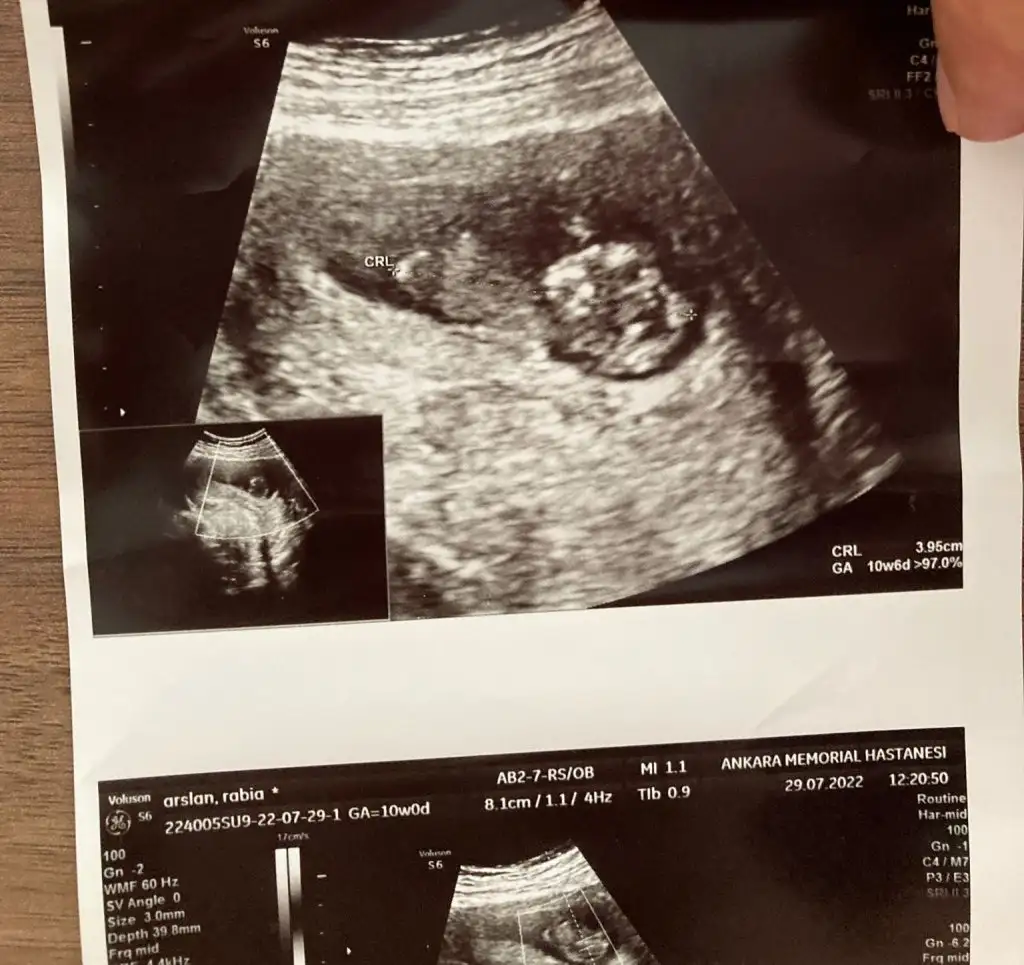

10 haftalık tahmin alabilirmiyiz

Ben 11-12 haftalardan sonrasını az çok öğrendiğim kadarı ile tahmin etmeye çalışıyorum sizinkisi çok küçük :)

Canm 12 haftadayiz tahminde bulunur musun

Eklentiler

• IMG20220801121845.webp

23,8 KB · Görüntüleme: 73

• IMG20220801120709.webp

57,9 KB · Görüntüleme: 74

• IMG20220801120653.webp

69 KB · Görüntüleme: 82